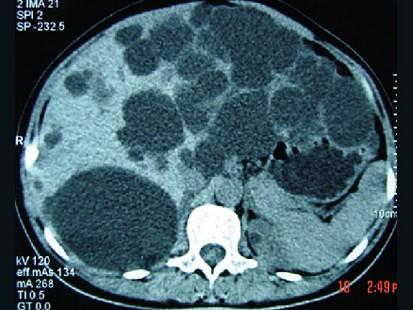

问题 女,20岁,右上腹胀,影像表现如图,最可能的诊断是 ( )

选项 A、肝脓肿并肾囊肿 B、多发性肝囊肿并多发性肾囊肿 C、多囊肝并肾多发囊肿 D、肝淋巴管瘤并多发性肾囊肿 E、先天性肝内胆管扩张并多囊肾

答案 C